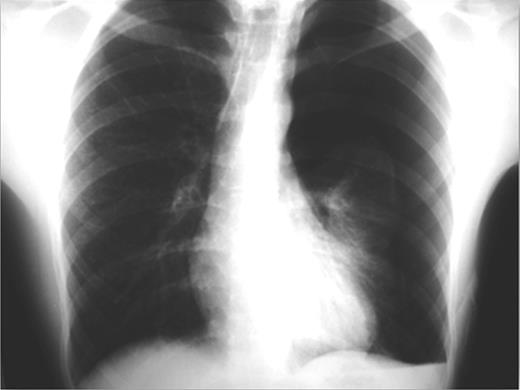

On emergency basis, the patient was managed with bilateral tube thoracostomy through the fifth intercostal spaces. During hospitalization, both lungs were gradually expanded; the use of continuous aspiration was necessary for a couple of days, in order to achieve complete expansion of the left lung (Fig. 2). Both chest tubes were removed on the fifth day of hospitalization. Next day the plain X-ray revealed recurrence of pneumothorax on the left side (Fig. 3). A chest tube was reinserted. Continuous suction was used and complete expansion of the left lung was succeeded. The tube was removed after 5 days; no recurrence took place at this time. During the next 3 days the patient remained under observation; serial physical examinations and chest X-rays were normal and the patient was discharged home.

Complete bilateral lung expansion after insertion of chest tubes.